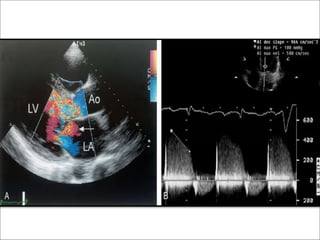

CW doppler

• The simplest approach is the comparison of the density or

darkness of the envelope of the antegrade aortic flow and the

regurgitant jet.

• The larger the regurgitant volume,the darker the regurgitant jet is

on CW doppler.

• Shape of the jet

• Highest velocity in early diastole – 4-6m/sec.

• Mild AR- jet shape is flat.- compliant LV allows slow and modest

increase in LV pressure and aortic diastolic pressure is

maintained.

• Severe AR – steeper slope - increasing LV pressure and more

rapidly decreasing aortic pressure leads to rapid deceleration of

the regurgitant jet velocity.

Slope of AR ,PHT

• The deceleration of jet velocity can be described as either

the slope or the pressure half time of the jet.

• A pressure half time less than 250 msec or a slope

greater than 400cm/sec2 is an indicator of severe AR.

• Affected by aortic compliance,blood pressure,LV size,

compliance of LV.

Slope(cm/sec2) PHT(msec) DT (msec)

Mild <250 >500 >1800

Moderate 250-400 250-500 800-1800

Severe >400 <250(200) <800